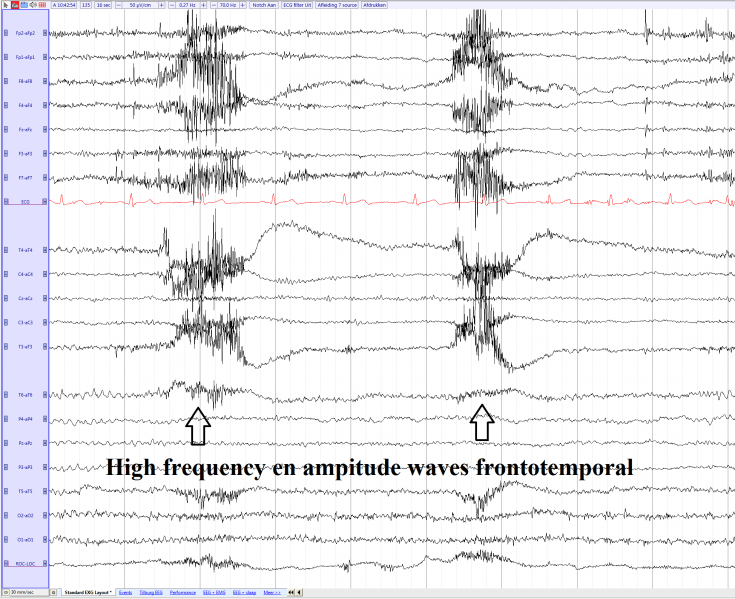

Muscle artifacts frontotemporal during chewing (source)

current16:35, 16 May 2017Thumbnail for version as of 16:35, 16 May 20171,949 × 1,589 (300 KB)EEGpedia (Talk | contribs)Muscle artifacts frontotemporal during chewing (source)